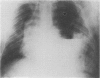

A 30 year old man developed severe respiratory distress during upper gastrointestinal endoscopy. He had a short oesophagus and part of the stomach was intrathoracic. Air-insufflation during endoscopy caused distension of the stomach inside the chest leading to respiratory distress. When part of the stomach is intrathoracic, the endoscopist should be cautious and the possibility of respiratory embarrassment kept in mind during air-insufflation.